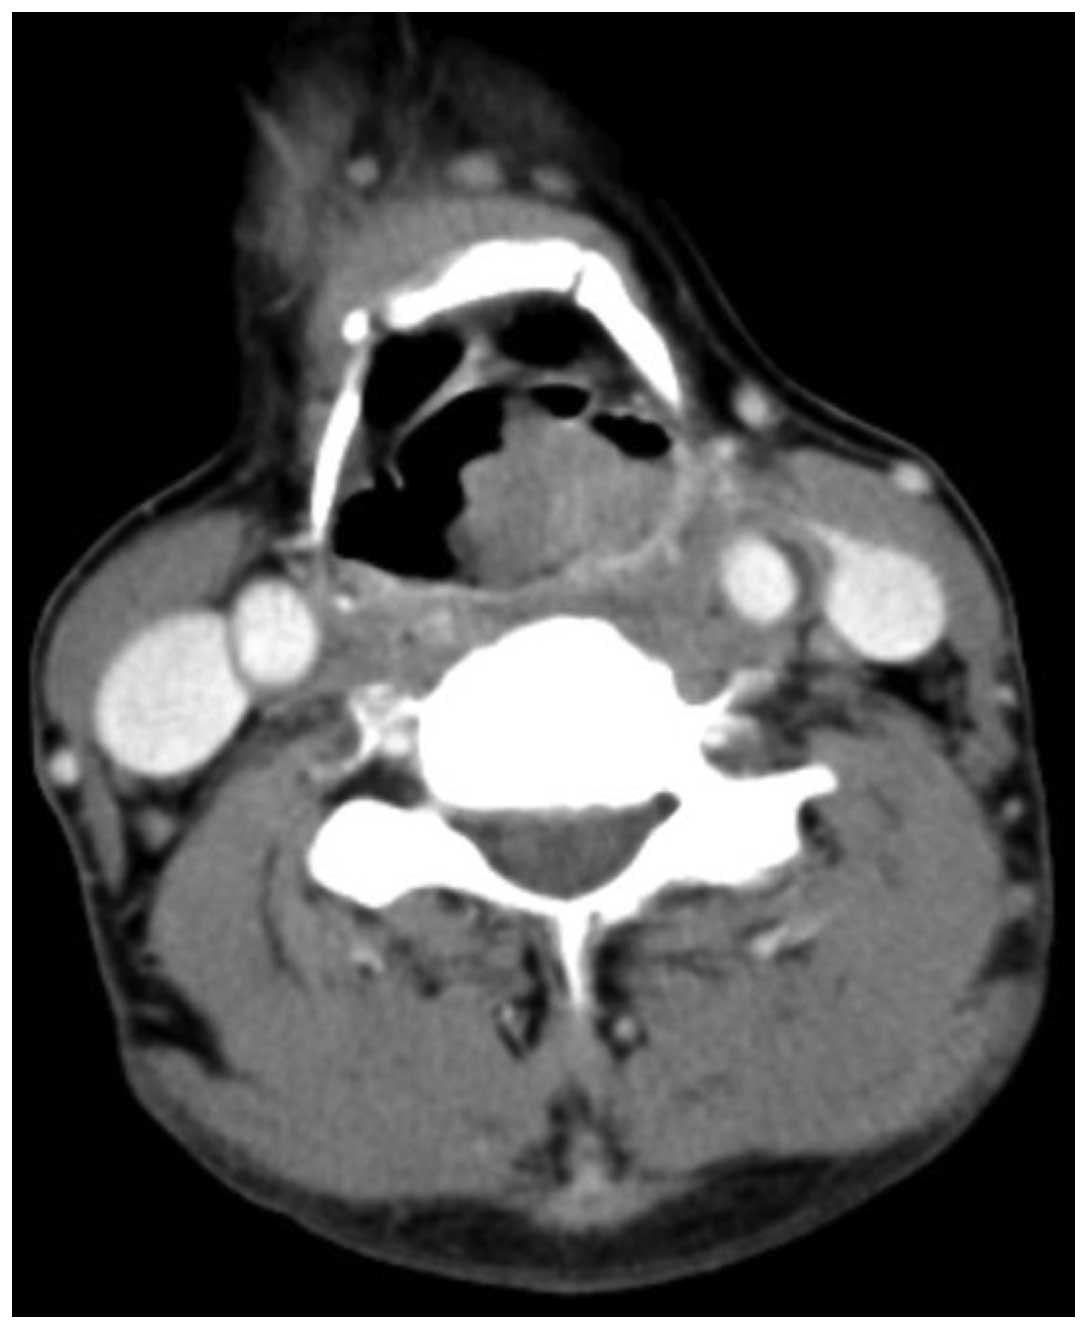

A 55-year-old male was admitted to the Department of Otolaryngology and Head and Neck Surgery, Sir Run Run Shaw Hospital, Medical College of Zhejiang University (Hangzhou, China) complaining of a mass on the left side of the neck, which had been present for six months. The patient reported that the mass had increased rapidly over the two preceding months. The patient stated there was no tenderness or paresthesia, however, the mass had been punctured and pus had been extracted at the Jiangshan Beilin Hospital (Jiangshan, China). An endoscopy revealed a 1.5-cm submucosal mass in the left pyriform sinus, which extended to the lateral wall (Fig. 1). The posterior pharyngeal wall, vocal cords, subglottic region and the base of the tongue appeared to be healthy. Computed tomographic (CT) examinations demonstrated a soft tissue mass in the left pyriform sinus and a 4.4×4.1-cm lesion, which was not well defined from the surrounding healthy soft tissue on the left side of the neck (Fig. 2).